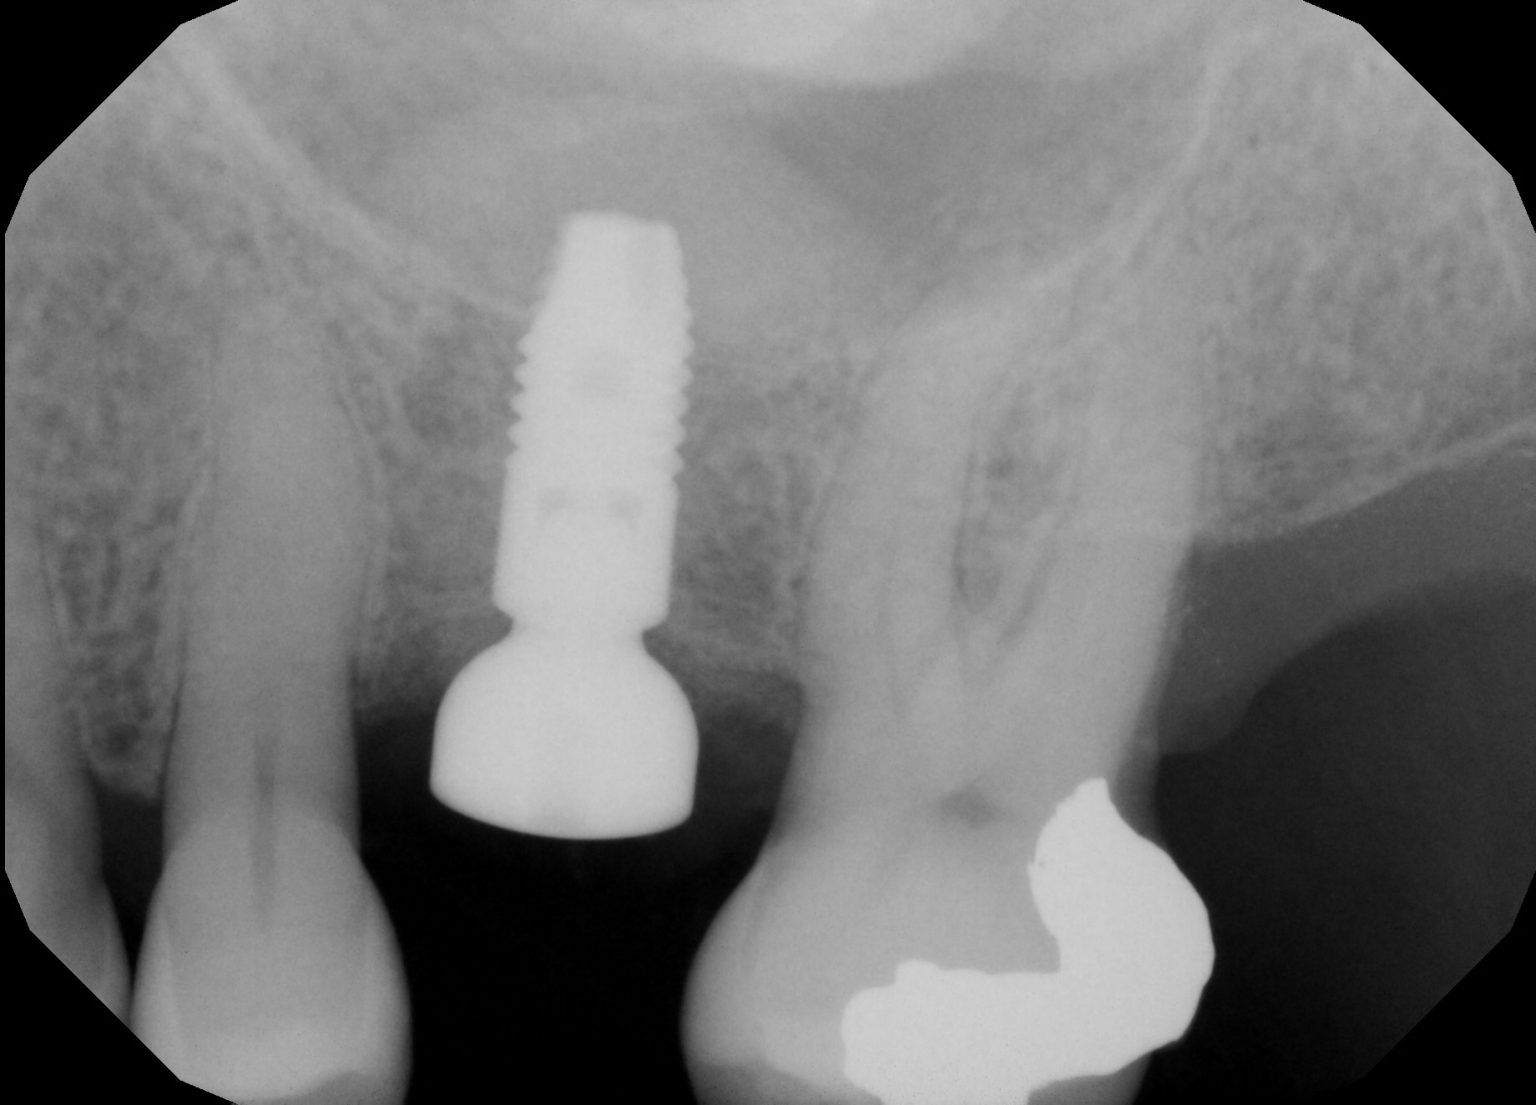

from regenperiotx.com